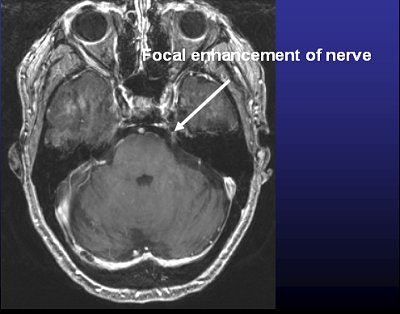

![]() |

| Above, frameless radiosurgery for TN. Below, three months after treatment. Images courtesy of Dr. Kevin Murphy and the University of California, San Diego, department of radiation oncology. |

UCSD started treating TN with the Trilogy system about a year ago, performing one to two procedures on a monthly basis. Initially, they reserved linac-based surgery for TN patients when other surgeries had failed, he said.

"We treated three patients who didn't want further gamma knife procedures with the bolted headframe. So far, all three are pain-free and they're very happy. Usually in a week to a month their pain goes away," he said.